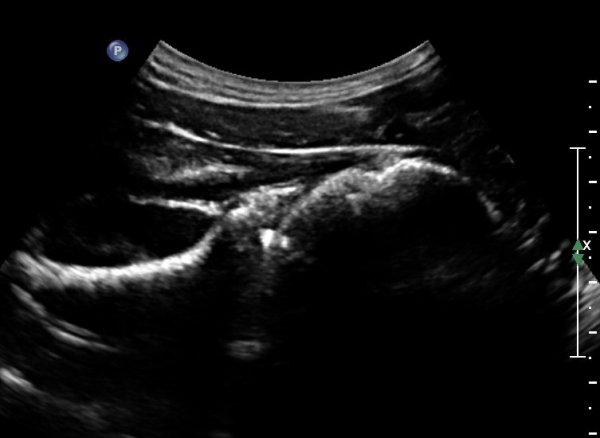

¾î±ú µÚÂÊ È¾´Ü¸é°Ë»ç¿¡¼­ °üÀý¿Í(glenoid) ³»Ãø¿¡¼­ ¸¹Àº ¾çÀÇ ¼ö¾×Àú·ù°¡ °üÂûµÈ´Ù(»çÁø 1, 2).

ÄÁº¤½ºÅ½ÃËÀÚ¸¦ ÀÌ¿ëÇÑ ¾î±ú µÚÂÊ È¾´Ü¸é°Ë»ç¿¡¼­ °üÀý¿Í ³»Ãø ¼ö¾× Àú·ù¿Í °üÀý¿Í¼ø ÆÄ¿­ÀÌ

°üÂûµÈ´Ù(»çÁø 3, 4, 5, 6).